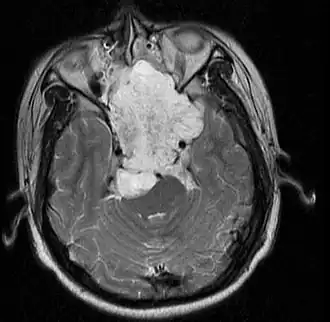

Хордома — редко встречающееся новообразование, считается, что она происходит из остатков нотохорда (эмбрионального предшественника скелета), но достоверных доказательств этого пока что не обнаружено. Опухоль локализуется преимущественно в крестцово-копчиковом сегменте позвоночника или же в затылочно-базилярной области черепа.

Макроскопически опухоль представляет собой узел, покрытый толстой капсулой — дольчатый, на разрезе серовато-белого цвета, с наличием очагов некроза.

Микроскопически опухоль полиморфна, клетки ткани опухоли разного размера и формы, чаще напоминают пузырьки с мелкими гиперхромными ядрами, и большими вакуолями в цитоплазме.